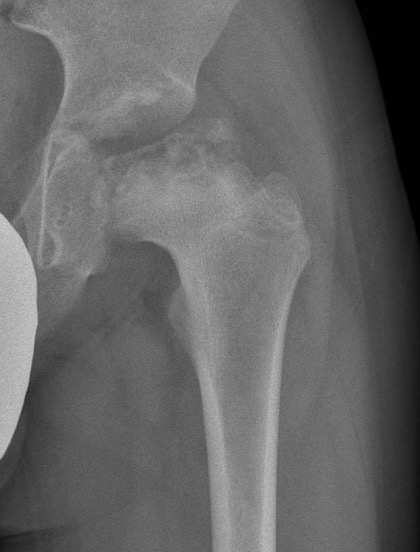

XRay - Fragmentation of Physis

XRay

- Better defined shape

- Return of bone density

Xray - May have flattening of the head and neck

Catterall

Technique

- uses AP & lateral xray

- 4 groups

- significant inter & intra-observer error

Group I

- < 25% involved

- anterocentral head

Group II

- 25-50% head

- anterolateral region / lateral column intact

Group III

- 50-75% head involvement

- moderate collapse

Group IV

- 100% of head sequestered

- severe collapse

Catterall "Head at Risk" Signs

Only lateral subluxation shown to be prognostic

5 Xray

1. Lateral subluxation head

2. Lateral epiphyseal calcification

3. Gage Sign - V shaped defect in lateral physis

4. Horizontal physis angle

5. Metaphyseal cysts